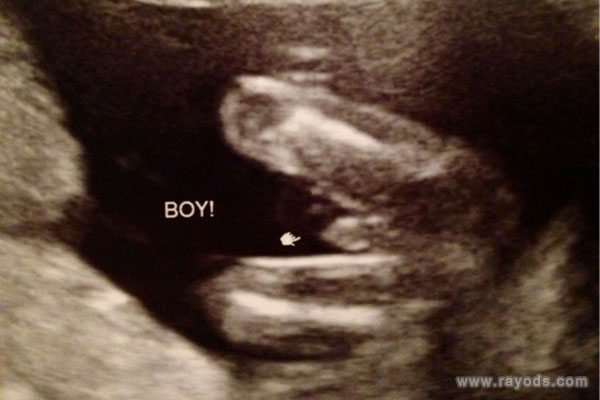

b超可以精确测量宝宝身体的各个数据,看器官发育是否正常等,但现在b超看胎儿似乎已经演变成了可以看性别的方法和途径。据了解,网上有不少关于b超看男女的方法,看起来似乎有理有据,有孕妈称b超时胎儿两腿间有圆圆的东西,都称这是宝宝生殖器,那这是男孩还是女孩呢?

b超胎儿两腿间有圆圆的东西

根据很多医生的解释称,如果胎儿双腿间有圆球的话,通常都是怀男孩的特征。当然,这需要在一个合理的孕周才可以准确判断,通常胎儿在22周之后,男胎女胎的生殖器官都已经发育完全了。这个时候B超可以看到圆圆的一个球,但是不能说就一定是怀的男孩,也可能是女孩。

很多宝妈都认为,如果胎儿两腿间有圆圆的东西和类似于小JJ的话,就可以认为是男孩。但B超检查时因为胎儿小JJ太小,很多时候都是看不清楚或者看不到的。因此,胎儿两腿间有圆圆的东西我们可以判定为是男胎宝宝的睾丸发育出来了,也可能是女胎宝宝的大***发育出来了。所以说,胎儿两腿间有圆圆的东西不一定是就是男孩,也可能是女孩哦。